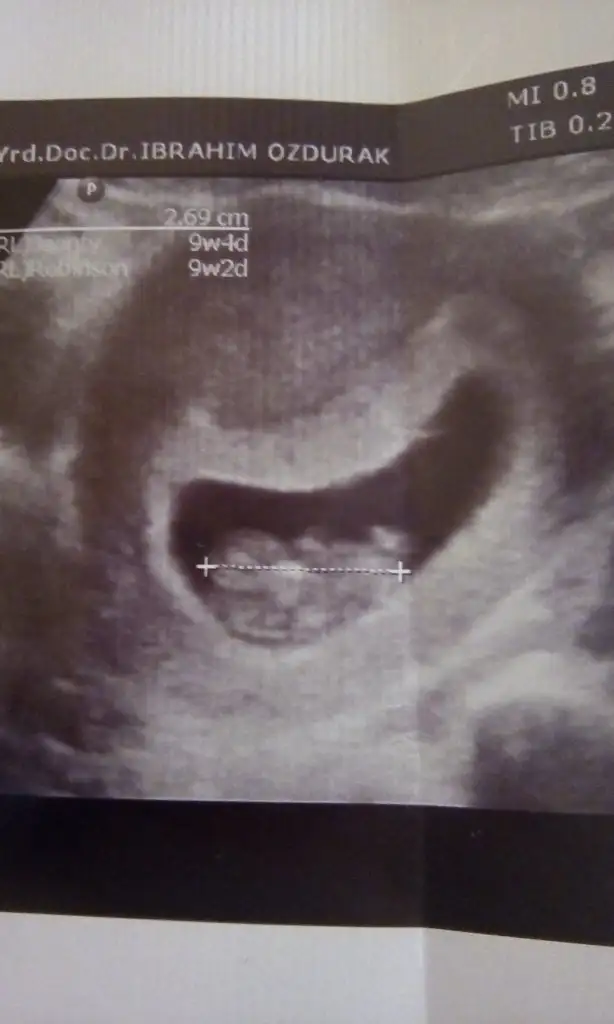

Arkadaşlar sizce cinsiyeti nedir bebeğimin

ErkekArkadaşlar sizce cinsiyeti nedir bebeğimin

Ulturasyon kalitesi cok düşük net değil resim aslindaTeşekkür ederim sağol canım hayırlısı olsun

Erkek bence canim ayak kısmı baya yukarda duruyorBi tane daha yükledim Can'ım ya belki bu daha nettir

Evet canım net gördüm ordaki cikintiyiFindik2 sen benim minigin cinsiyete ne demistin cnm,unuttum ya.bak resimde işaretlediğim yere bak sana bi çıkıntı var yakınlaştırıp bak.